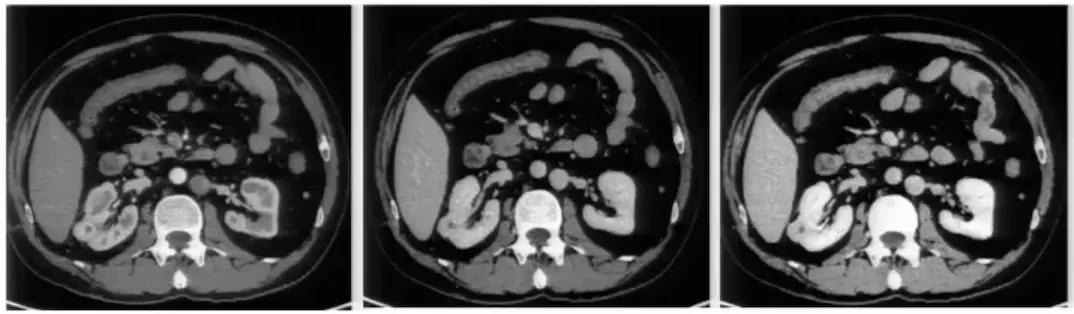

先上图:

图1:腹膜后方下腔静脉处于腹主动脉左侧;左肾静脉出左肾门后,汇入下腔静脉路径缩短